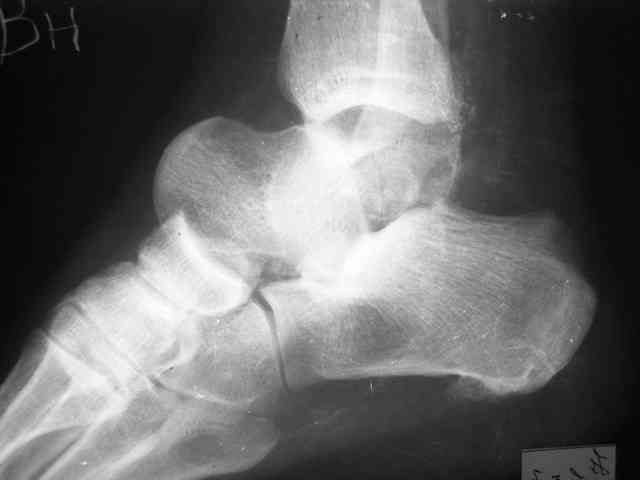

Уважаемый Александр! Как обещал представляю Р-граммы и операционные фото.

Ваши (лично ваши) рекомендации - астрагалэктомия-аппаратный пяточно-большеберцовый артродез с одновременным удлинением голени - правильно?

А удлинять голень в условиях плохих сосудов как? В смысле как потянутся склерозированные сосуды? Удлинять-то надо около 3 см.

Мы обычно удлиняли на 2 уровнях по 1,5-2 см. В конце концов, можно и не удлинять, укорочение компенсировать вкладками в обувь.